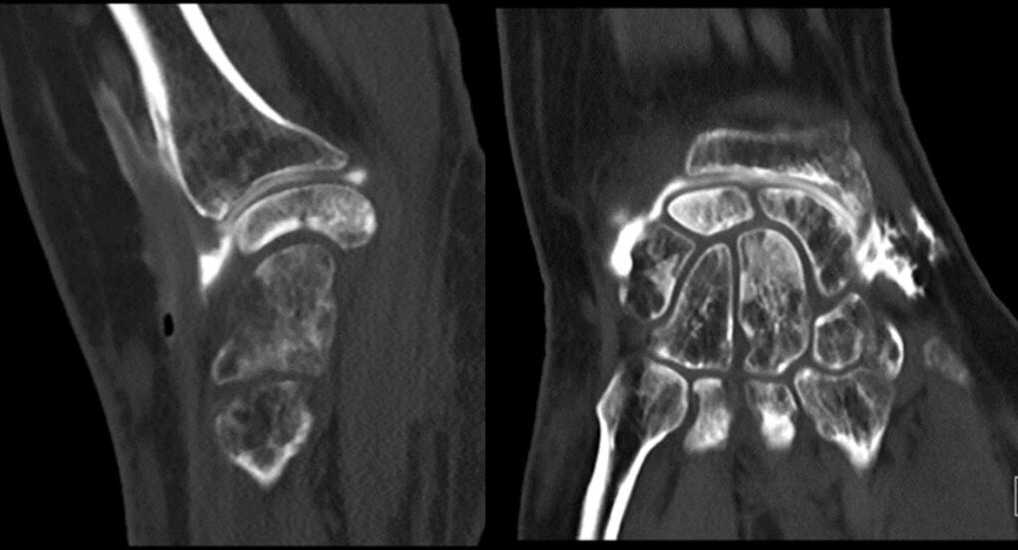

Here, we present two cases of Kienböck’s disease classified as Lichtman stage IIIc, characterized by complete osteonecrosis and a coronal fracture of the lunate, without associated cartilage damage. Both patients underwent a medial closing wedge osteotomy of the radius combined with compression screw fixation of the lunate fracture. The two patients were female, aged 42 and 47 years, with a history of wrist pain. Pre-operative imaging included standard wrist radiography, which revealed a negative ulnar variance (radiographic ulnar index), computed tomography (CT) confirming the presence of a lunate fracture, and MRI demonstrating osteonecrosis (showing a hypointense signal on T1-weighted sequences and a hyperintense signal on T2-weighted sequences, with no gadolinium enhancement). No signs of carpal instability or cartilage degeneration were observed in the surrounding structures.

- Patient B: A 47-year-old left-handed housewife presented with a 1-year history of left wrist pain. She reported no history of trauma, was a non-smoker, and had no significant medical history (Fig. 4, 5, 6).

Figure 4: X-ray radiographic ulnar index of −3.7 mm.

Figure 5: Computed tomography scan.

Figure 6: Magnetic resonance imaging.